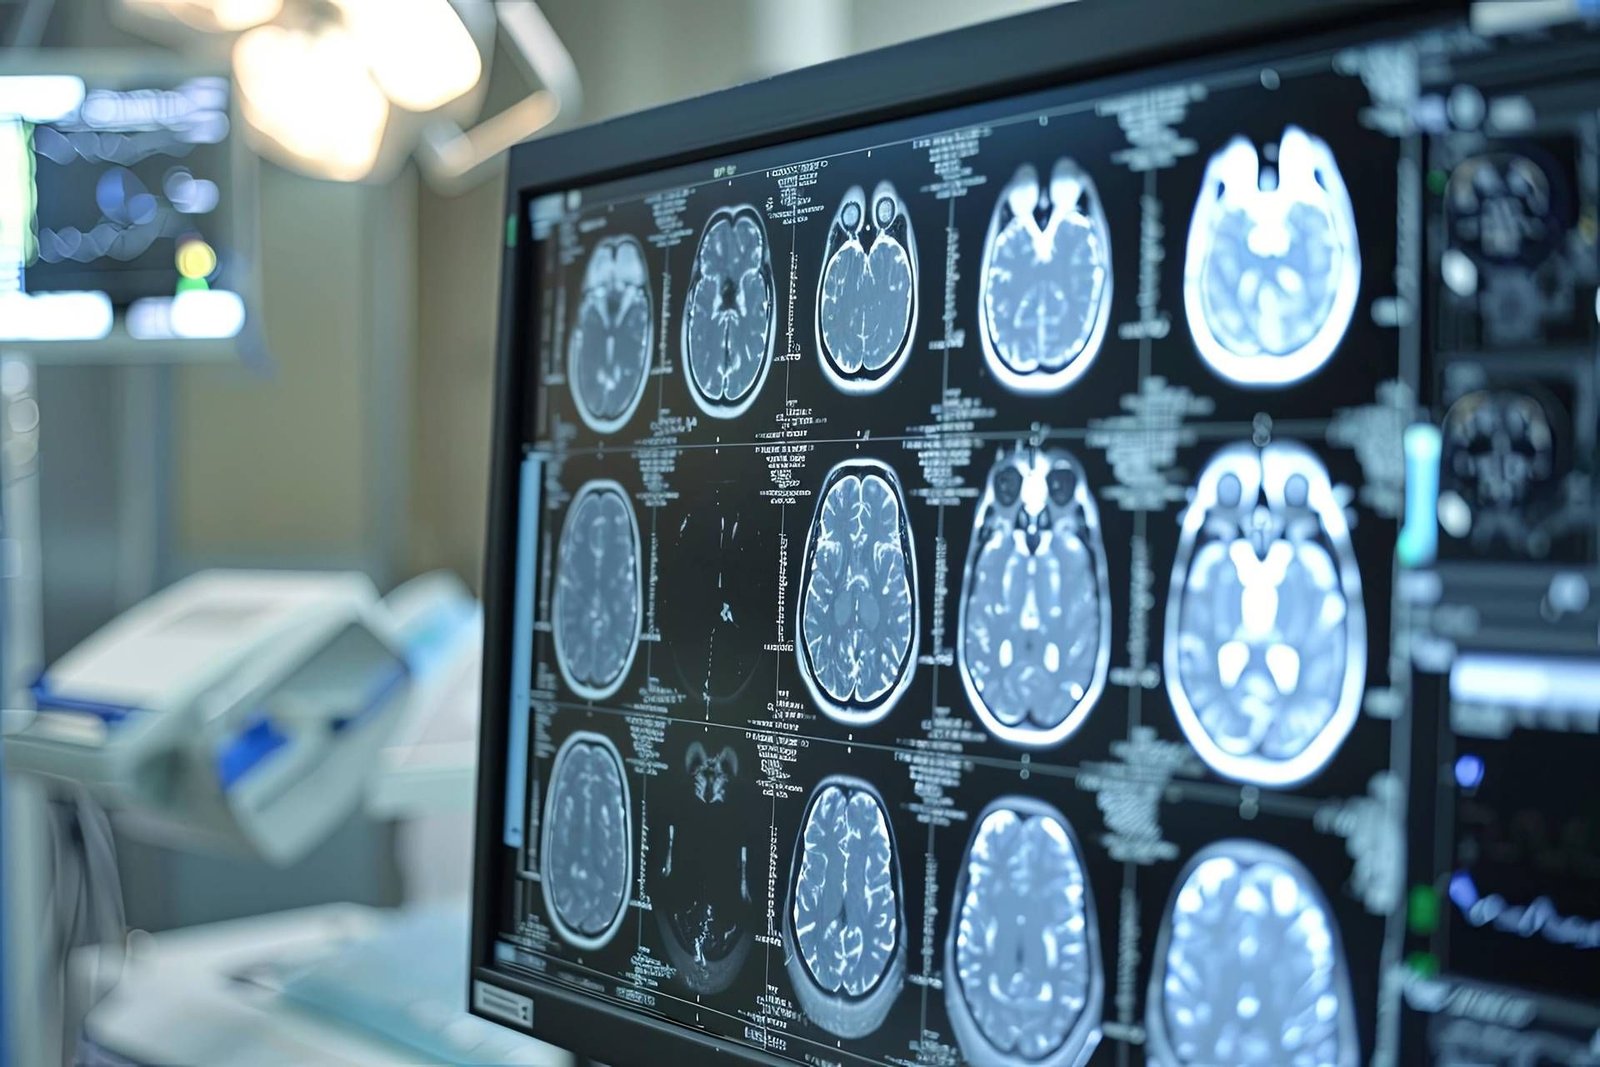

L’ictus ischemico rappresenta una delle principali sfide sanitarie a livello globale, colpendo ogni anno circa 12 milioni di persone. In Puglia, come nel resto d’Italia, la questione è particolarmente rilevante, considerando che il 20-30% dei pazienti che hanno già subito un ictus rischia una recidiva. Recentemente, Bayer Italia ha annunciato i risultati preliminari dello studio di fase 3 Oceanic-Stroke, che potrebbe segnare un cambiamento significativo nella prevenzione secondaria di questa patologia.

Lo studio ha coinvolto 22 centri clinici in Italia, contribuendo in modo determinante alla robustezza scientifica dei risultati globali. Tra questi, alcuni centri pugliesi hanno partecipato attivamente, dimostrando l’importanza della ricerca locale nel contesto internazionale. I dati raccolti dai centri italiani hanno permesso di valutare l’efficacia dell’inibitore del Fattore XIa, asundexian, in aggiunta alla terapia antiaggregante standard.

Asundexian ha mostrato una riduzione significativa del rischio di ictus ischemico rispetto al placebo, senza aumentare i sanguinamenti maggiori. Questo è un aspetto cruciale, poiché le terapie attualmente disponibili non sono sempre sufficienti a prevenire le recidive. Secondo il dottor Andrea Zini, direttore della Neurologia e Rete Stroke dell’IRCCS Istituto delle Scienze Neurologiche di Bologna, “asundexian rappresenta una nuova frontiera nella prevenzione dell’ictus”.